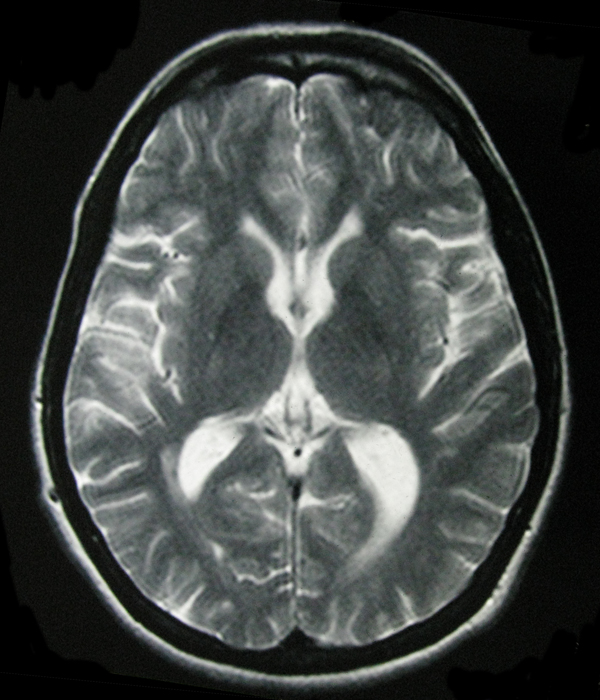

- My Brain in 2009